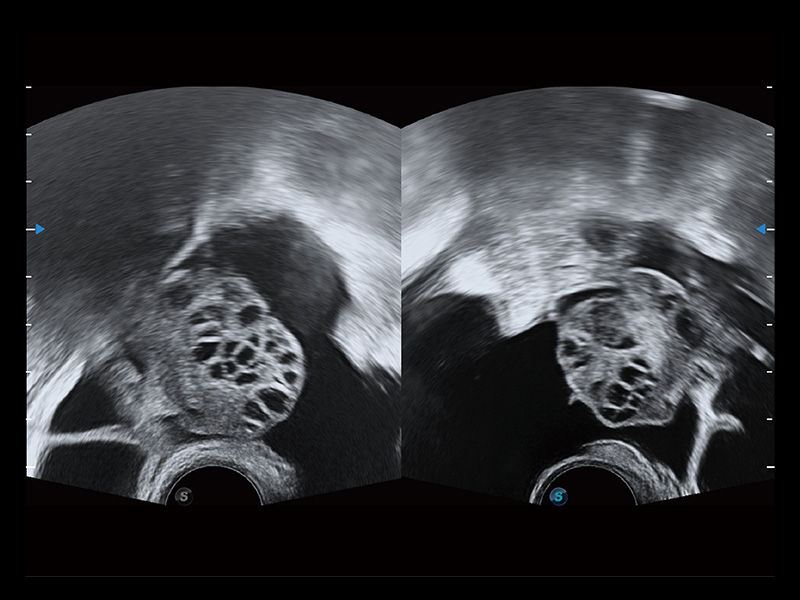

临床图

超声引导下双侧卵巢穿刺取卵

卵巢多囊样改变